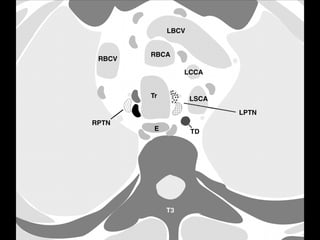

2R. Right upper paratracheal LNs

• Upper border: upper border of manubrium.

• Lower border: intersection between lower

border of left innominate vein and trachea.

• Medial border: midline of the trachea.

2L. Left upper paratracheal LNs

• Upper border: superior border of the

manuibrium.

• Lower border: superior border of aortic

arch.

4R. Right lower paratracheal LNs

4L. Left lower paratracheal LNs